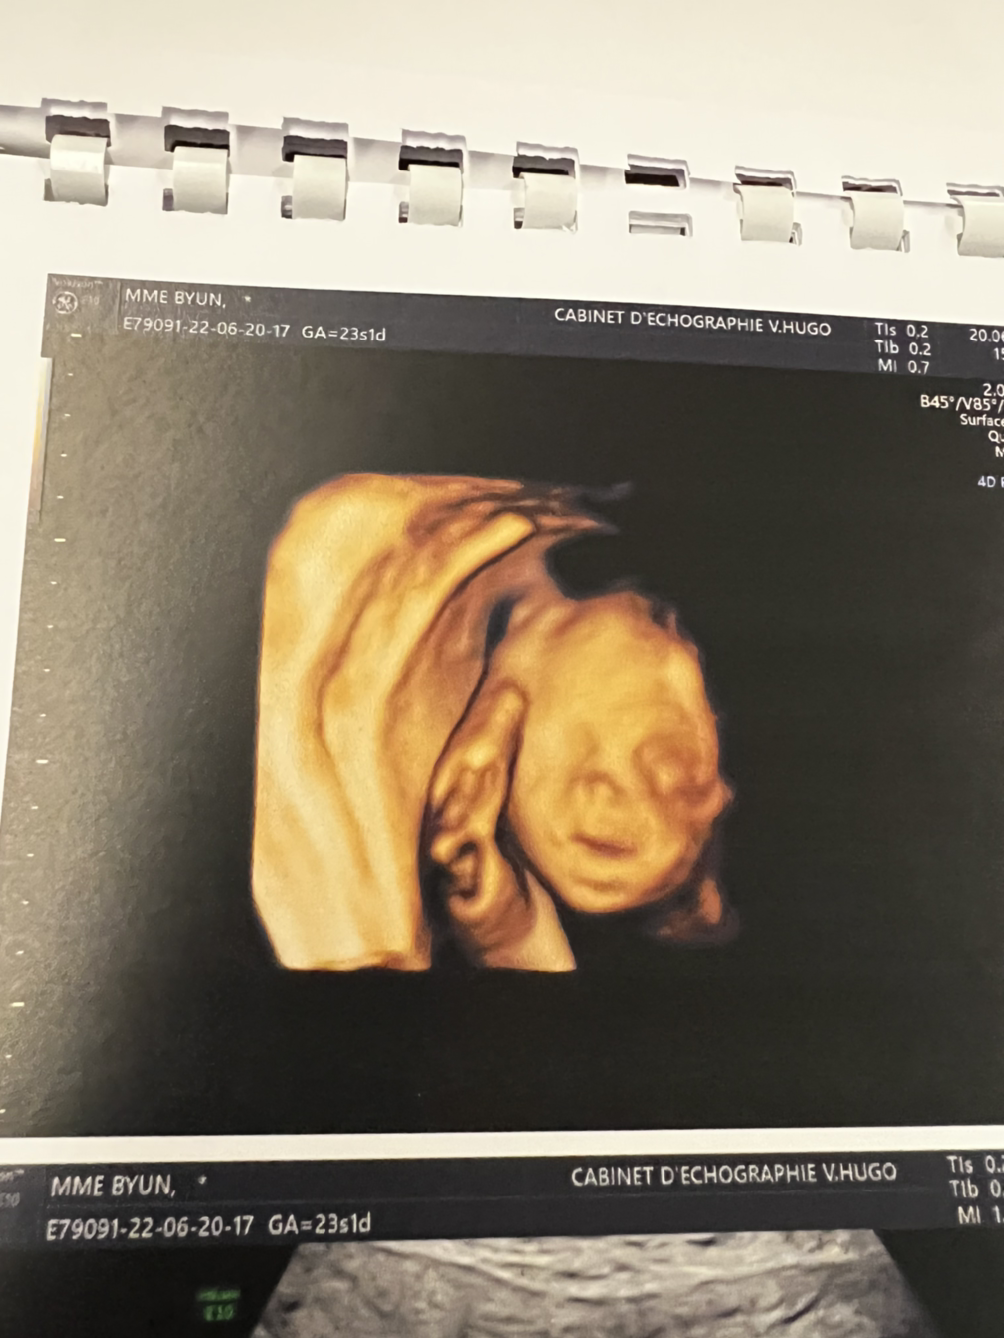

그런데도 아무런 불만없는 듯 건강하게 잘 자라줬다. 그리고, 이제 23주라서 눈코입 선명하게 얼굴이 보였다.

진짜 왔구나, 네가. 기쁨아.

그렇게 오늘은 초음파 검사를 했고, 영어를 거의 못하는 초음파 전문 의사가 봐주었다.

그 할아버지 의사샘은 무려 40분간 초음파를 봐주었다. 계속해서 !@%#$^ 정상, #$%$&$&$ 정상 이러는데, "정상"이라는 단어 밖에 알아듣지 못했다. 둘째가 진짜 궁금하고 계속 지켜보고 싶었지만, 나는 잠들어버렸다.

그렇게 다 "정상"이라는 말만 끝으로 듣고, 잠에서 깨 나왔다

하지만, 기쁨이, 너 얼굴을 보니 이젠 진짜 실감 난다.

105일 뒤에 만나자.